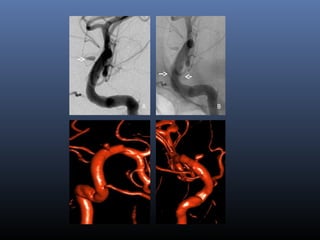

Further evolution –

flow diverters (stents)

Dissections with blister

EVD

2-overlapping Enterprise stents

A B C

D E F